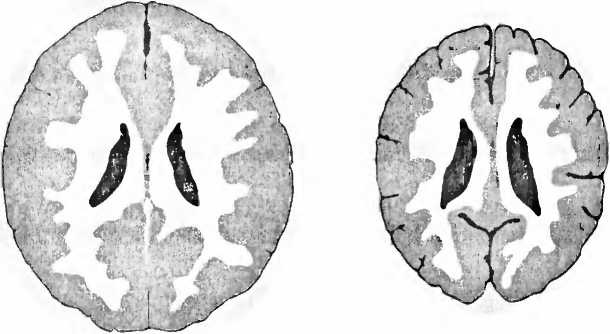

Иллюстрация к книге — Мы - это наш мозг. От матки до Альцгеймера [i_009.jpg]

Рис. 6. Справа — томограмма мозга сильно запущенного трехлетнего ребенка, и для сравнения — томограмма мозга ребенка такого же возраста с нормальным развитием мозга (слева). У запущенного ребенка мозг значительно меньше, с увеличенными желудочками вентрикулами, полостями, черного цвета), по сравнению с мозгом нормально развивавшегося ребенка того же возраста. Кроме того между мозговыми извилинами видны увеличенные пространства из-за сморщивания (атрофии) коры больших полушарий (В. D. Perry, 2002).